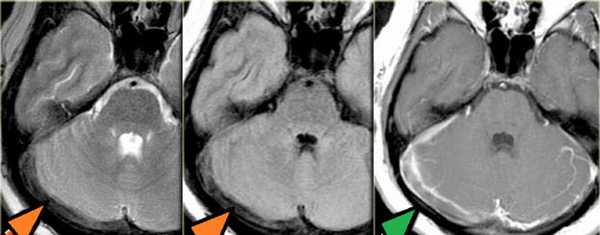

Тромбоз правого поперечного синуса - гипоинтенсивные участки по Т2 (внутриклеточный дезоксигемоглобин).

МРТ головного мозга: справа (зеленая стрелка) на Т2-взвешенном изображении отмечается имеющийся в норме феномен «пустоты потока» от правого сигмовидного синуса и яремной Вены. Слева (оранжевая стрелка) отмечается аномально высокий сигнал, в результате, вероятнее, тромбоза. Для подтверждения синус-тромбоза и окончательного определения локализации и протяженности тромбоза необходимо проведение МР-венографии.

МРТ головного мозга: отмечается сочетание вазогенного (оранжевая стрелка), цитотоксического отека и кровоизлияния (зеленая стрелка). Данная МР-картина, а также расположение патологической зоны в проекции височной доли, заставляет задуматься о геморрагическом венозном НМК вследствие тромбоза вены Лаббе. Для подтверждения необходимо проведение МР-венографии или МРТ с контрастным усилением.